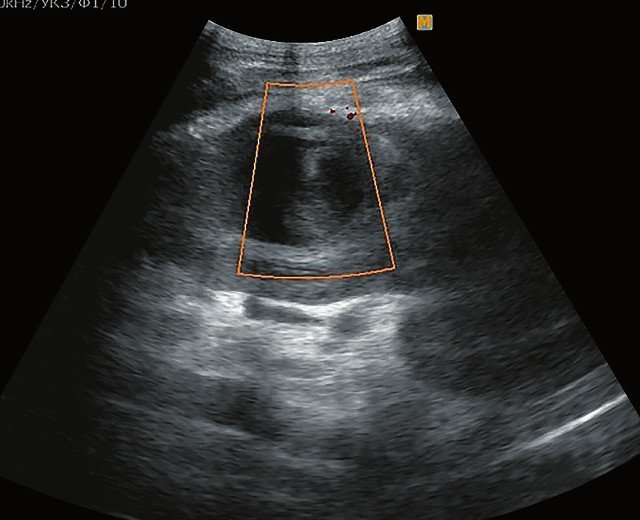

ЦДК сосудов почек: что это и как проводится

Раздел: Фотоэссе